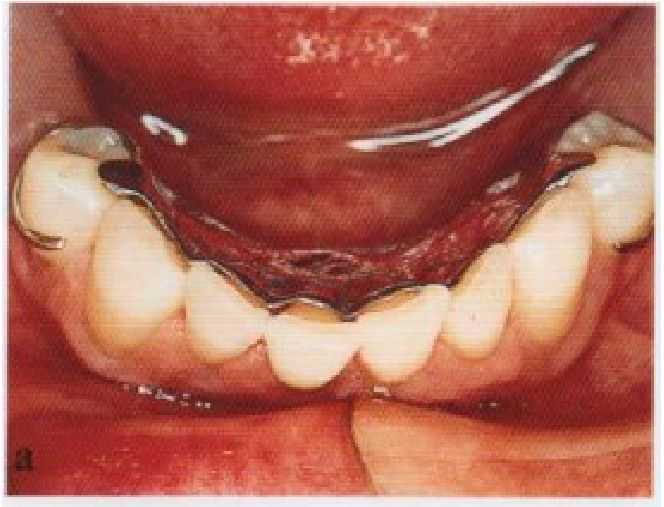

Рис. 11-4. Функциональный оттиск: (а) каркас с плотно прилегающими базисами установлен на ткани протезного ложа и на седла оказывается давление. Образующееся в результате этого смещение седел приводит к приподниманию дуги над язычными поверхностями передних зубов. Если этого смешения не произошло и границы седел являются приемлемыми, то получение функционального оттиска не

____требуется; (б) окантовка дис-

тального отдела язычного борта с помощью зеленой термомассы; (в) оттиск, полученный с помощью цинкоксидэвгеноловой оттискной пасты.